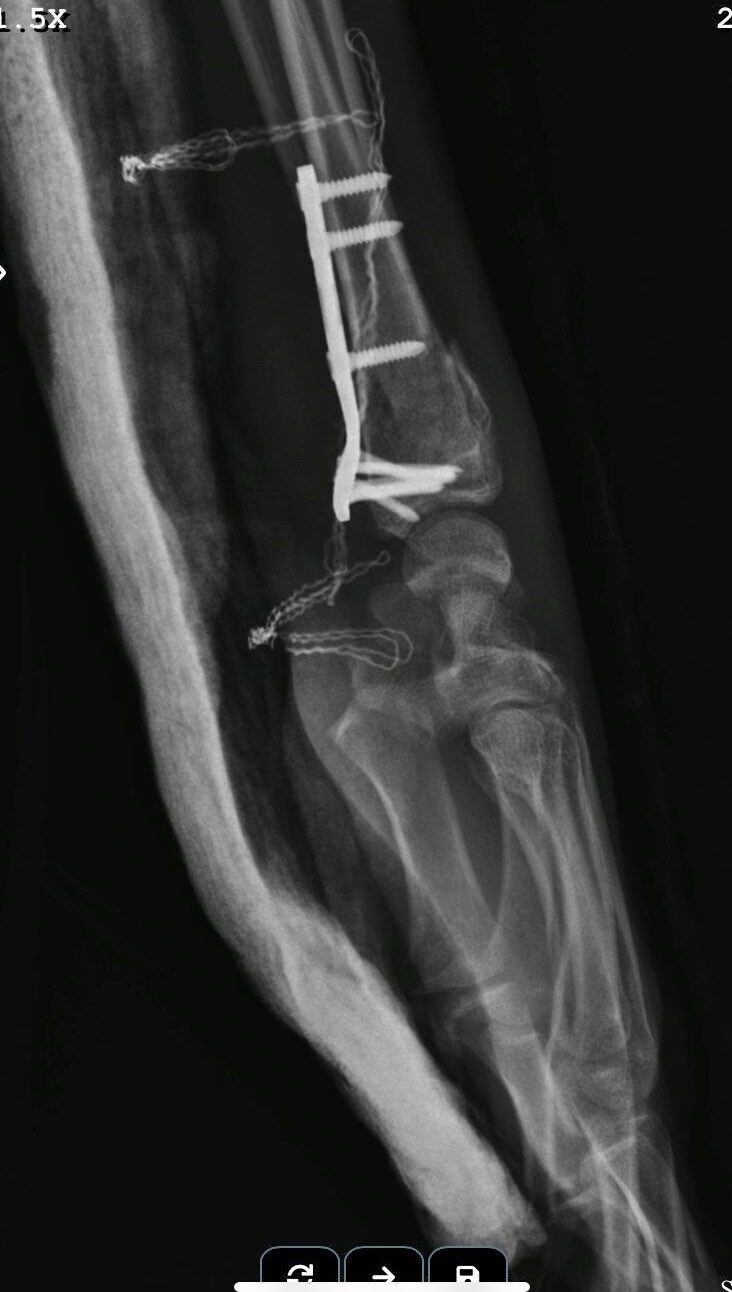

25 Eylül tarihinde Gündoğdu Mahallesi Cumhuriyet Bulvarı’nda gerçekleşen kazada, Birol T. yönetimindeki 34 HBF 007 plakalı otomobil ile Yusuf Gündoğmuş’un kullandığı 26 AIZ 906 plakalı motosiklet çarpıştı. Her iki sürücü de yaralanırken, motorcu Yusuf Gündoğmuş’un durumu oldukça kritikti. Kazanın ardından uzun bir süre Eskişehir Şehir Hastanesi’nin yoğun bakım ünitesinde tedavi gören genç adam, birden fazla operasyondan sonra hayata döndü. Ailesinin dua ve destekleriyle, tedavi süreci devam ediyor.

Yusuf Gündoğmuş’un tedavi sürecini detaylandıran babası, “Oğlum beş gün boyunca entübe edildi ve ciğerleriyle ilgili ciddi sorunlar yaşandı. Şükürler olsun, doktorlarımız sayesinde bu aşamayı atlattık. Oğlumun tedavisi ve sağlığı için sürekli dua ediyoruz,” dedi. Oğlunun sağlık durumu hakkında iyimser olduklarını belirten baba, yapılan operasyonların başarılı geçtiğini ifade etti.